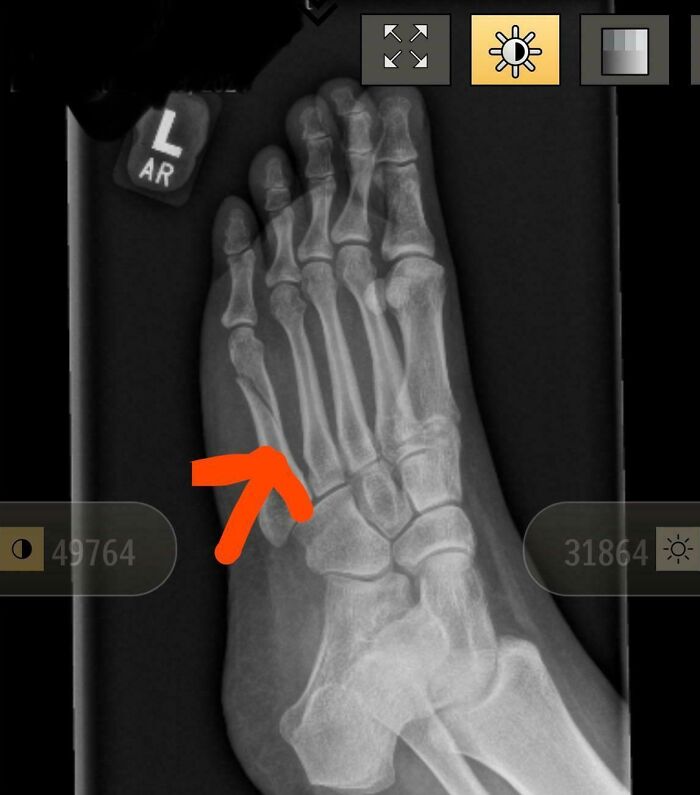

2 Weeks Ago My Youngest Daughter Broke Her Leg 1 Week Before Our Holiday. Yesterday I Broke My Own Leg (On Holiday). Poor Sis And Mom